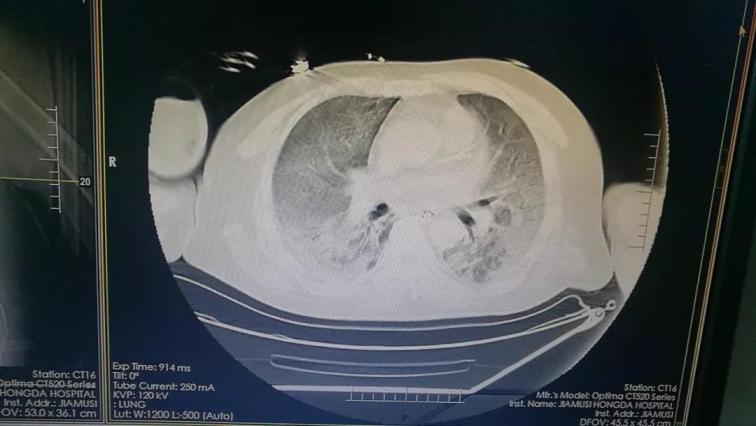

5月15日佳木斯大學(xué)宏大醫(yī)院重癥醫(yī)學(xué)科(ICU)收治1例急性上呼吸道重癥感染的患者。該患者繼往有腎病綜合征病史,在鶴崗市三甲醫(yī)院診斷為頑固性ARDS。CT片顯示雙肺透過(guò)度減低,并見(jiàn)大片高密度影,部分病灶實(shí)變,其中可見(jiàn)支氣管氣相,俗稱(chēng)“大白肺”。當(dāng)?shù)蒯t(yī)院認(rèn)為此患者已經(jīng)沒(méi)有搶救價(jià)值了。